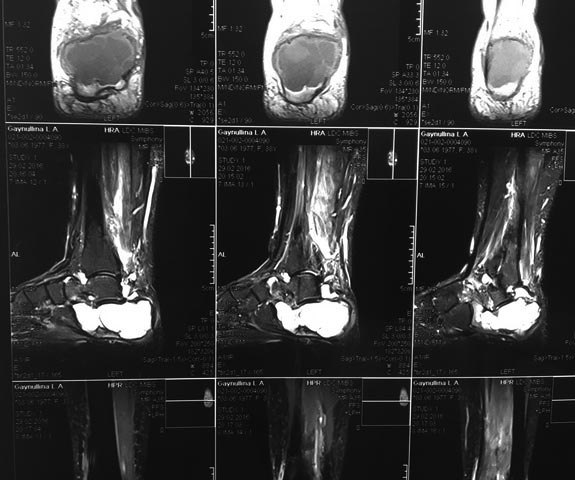

Пациентка с большой аневризмальной костной кистой пяточной кости.

Пациентка Г., 38 лет. 1,5 года назад появились боли в левой пяточной

кости. Болей в покое и ночных болей нет. 08.09.15 операция: экскохлаеция

аневризмальной костной кисты, пластика деминерализованными костными

трансплантатами. По данным МРТ (29.02.16) костной

перестройки нет, вероятно произошел выход содержимого кисты в

пространство позади ахиллова сухожилия.